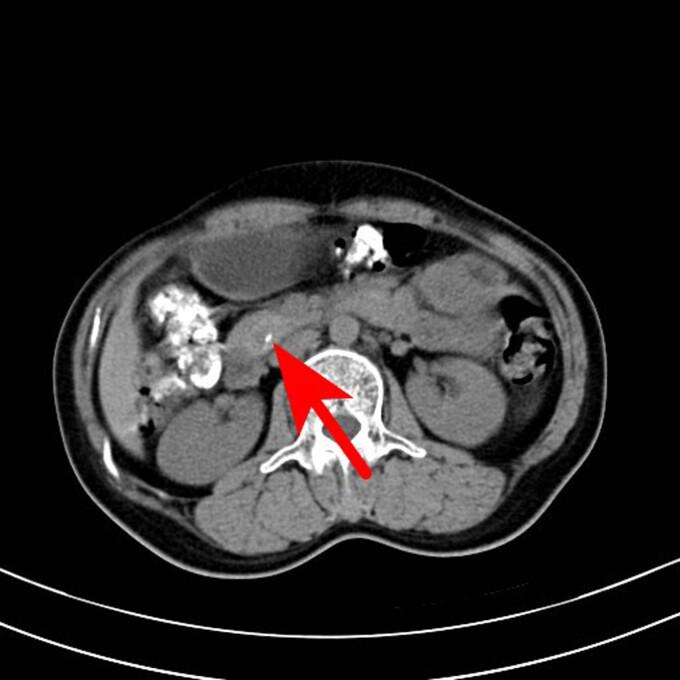

Ectopic thyroid is a rare malformation induced by a migration defect in the developing gland during embryogenesis. In 90% of cases, the ectopic thyroid is located in the lingual region, whereas it is extremely rare in the abdominal cavity, particularly in the pancreas. A 50-year-old female patient presented to the Taizhou First People's Hospital with a complaint of recurrent mid-lower abdominal pain and diarrhea for approximately a month. The abdominal computed tomography scan revealed a space-occupying lesion with abundant blood supply in the head of the pancreas during the consultation. This led to the suspicion of a neuroendocrine tumor. The doctor considered that this lesion in the head of the pancreas could be responsible for the patient's incontinence. A laparoscopic pancreaticoduodenectomy was performed after relevant tests were undertaken and contraindications were ruled out. The patient was diagnosed with ectopic thyroid of the pancreas through postoperative pathology. Ectopic thyroid can be considered in middle-aged and elderly women who present with a mass with abundant blood supply and an unknown diagnosis. Subsequent treatments should be decided after fine-needle aspiration cytology.